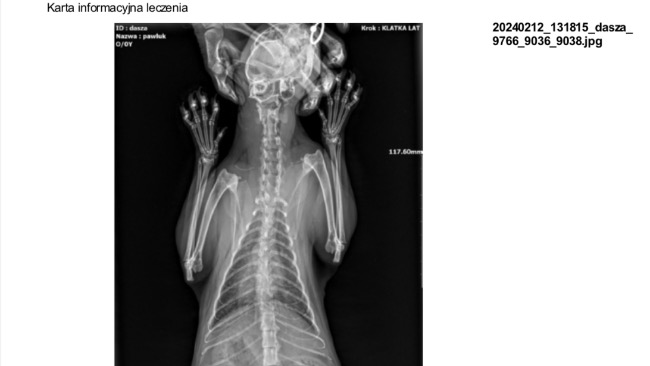

Wstawiam do zrzutki i postu fakturę, kartę leczenie i rtg.